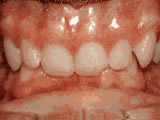

Open Bite Correction

Started treatment at age 13 with braces and a tongue-training crib appliance for 28 months to correct an open bite caused by thumb-sucking — now enjoys a normal bite.

Open bite - Front teeth don't touch Before Open bite - Front teeth don't touch after